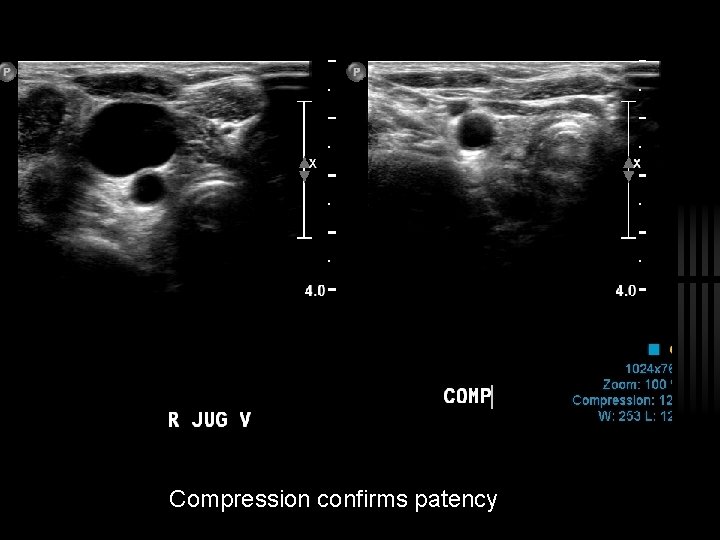

Compression confirms patency